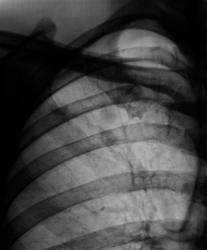

Флюорограмма 2007 год.

2.F-graf..JPG